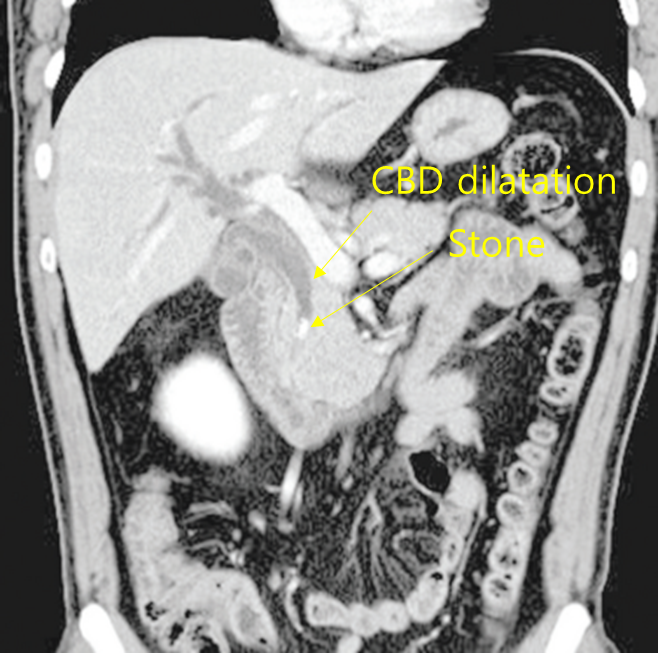

59세 여자가 2일 전부터 윗배가 아프고 열이 난다며 병원에 왔다. 구토를 하며 소변색이 진하다고 한다. 혈압 90/50 mmHg, 맥박 102회/분, 호흡 20회/분, 체온 38.9℃이다. 공막에 황달이 있다. 오른쪽 윗배에 압통이 있다. 혈액검사 결과는 다음과 같다. 복부 컴퓨터단층촬영 사진이다. 치료는?

백혈구 16,500/mm3, 혈색소 12g/dL, 혈소판 90,000/mm3, 총빌리루빈 6.5 mg/dL, 직접빌리루빈 4.7 mg/dL, 아스파르테이트아미노전달효소 331U/L, 알라닌아미노전달효소 190U/L, 아밀라아제 240U/L, 리파제 160U/L

Img | CT: 담관 확장, 담관내 담석 |

윗배 통증과 발열을 주소로 내원한 환자로, 황달, RUQ tenderness 등으로부터 급성 담관염을 의심할 수 있다. 혈액검사에서도 담즙 정체 소견이 확인되고 있으며, 결정적으로 CT 상에서 담관 내에 하얗게 담석이 관찰되고 이로 인한 담관 확장이 있다. 혈압이 저하된 상태로, ERCP를 시행하여 stone removal 및 내시경코쓸개길배액술(ENBD)로 bile을 제거해주어야 하겠다.

진단 | • US/CT: Bile duct dilatation, stone이 보일 수도 있음 • MRCP/ERCP: Proximal bile duct dilatation, filling defect 등 |